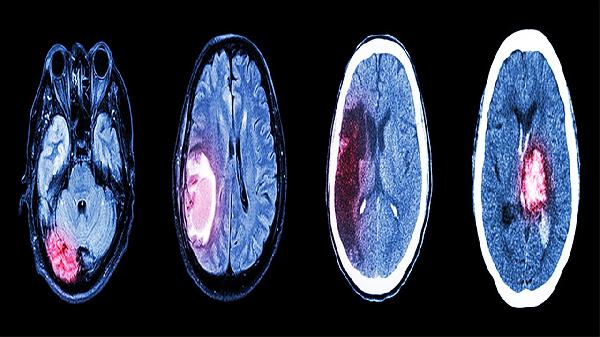

轻度闭合性颅脑损伤的患者通常会出现短暂的意识丧失,时间一般不超过半小时,可能伴随头痛、头晕、恶心、呕吐等表现。神经系统检查通常没有明显异常,而通过头颅CT或MRI等影像学手段,可能会发现正常或者仅有轻微的变化。这类损伤多由跌倒、车祸、运动时受伤等原因引起,脑部受损情况不严重,没有出现大出血或严重的脑挫裂伤。治疗上以休息和对症处理为主,医生可能会推荐使用布洛芬缓释胶囊、对乙酰氨基酚片等药物来缓解头痛,或者用甲氧氯普胺片控制呕吐。多数患者在1到2周内症状会逐渐减轻,预后较好。